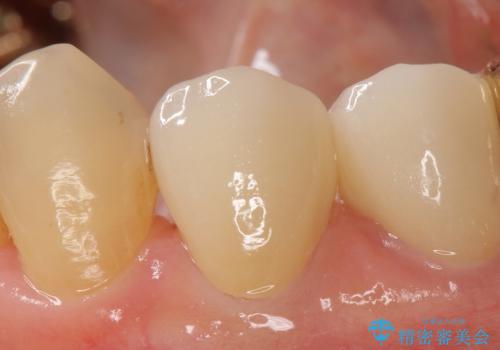

今回用いたオールセラミッククラウンはジルコニアフレームという白い素材の上にセラミックを盛っているため、審美性が非常に高いのが特徴です。

また、ジルコニアは人工ダイヤモンドの材料にも使われているほど高い強度を持っており、そのためオールセラミッククラウンは審美性だけでなく、奥歯やブリッジの補綴も可能とするクラウンです。